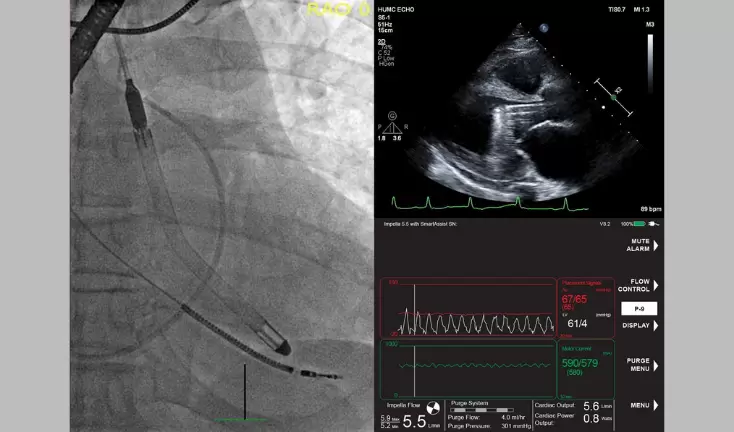

Press Releases Filter Filter Results Year 2026 (2) 2025 (3) 2024 (5) 2023 (5) 2022 (23) 2021 (17) 2020 (37) 2019 (35) 2018 (23) 2017 (24) 2016 (20) 2015 (25) 2014 (26) 2013 (31) 2012 (35) July 16, 2020 FDA Approves Data Streaming from the Impella Console, Setting the Stage for Artificial Intelligence Algorithms to Further Improve Patient Outcomes July 16, 2020 Abiomed First Quarter Fiscal 2021 Earnings and Conference Call Notification July 1, 2020 Study Finds 84% Survival Rate in Patients in Cardiogenic Shock and Other Challenging Cardiac Conditions with the New Impella 5.5 with SmartAssist June 16, 2020 Abiomed Launches Virtual Physician Education Program, CAMP PCI, to Improve High-Risk PCI Patient Outcomes June 15, 2020 Abiomed Appoints New Chief Medical Officer Charles Simonton, M.D. June 5, 2020 FDA Approves Abiomed’s First-in-Human Trial of Impella ECP, World’s Smallest Heart Pump June 3, 2020 Abiomed to Hold Fireside Chat at the William Blair 40th Annual Growth Stock Conference June 1, 2020 FDA Issues Emergency Use Authorization for Impella RP as Therapy for COVID-19 Patients with Right Heart Failure May 27, 2020 Abiomed to Hold Fireside Chat at Jefferies Virtual Healthcare Conference May 20, 2020 Abiomed to Host Virtual Clinical Data and Innovation Day May 19, 2020 PROTECT III Study Shows Placing Impella Prior to High-Risk PCI is Associated with Lower Mortality Compared to Bailout PCI April 30, 2020 Abiomed Announces Q4 FY 2020 Revenue of $207 Million and 28.1% Operating Margin April 29, 2020 Abiomed Expands Product Portfolio with Acquisition of Cardiopulmonary Support Technology (ECMO) to Improve Outcomes for Patients April 10, 2020 Abiomed Fourth Quarter Fiscal 2020 Earnings and Conference Call Notification March 25, 2020 Abiomed’s Response to the COVID-19 Pandemic … 5 6 7 8 …